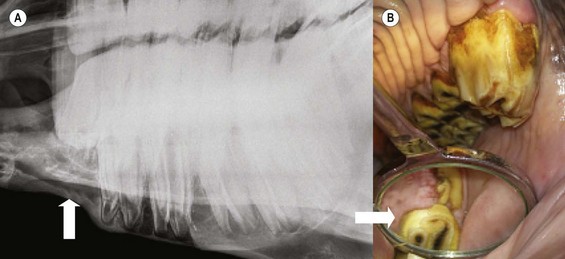

Fig. 8.9 (A) The supernumerary CT present at the caudal aspect of this maxillary CT row is overgrown due to absence of occlusal contact. Contact of the overgrowth with the caudal aspect of the lower 11 has caused it to displace caudally, causing a wide diastema (arrow) between it and the adjacent 11. (B) Intra-oral view of a supernumerary 212 that has overgrown and caused a diastema (arrow) to develop between it and the 211. The flat occlusal surface shows it has been reduced in the past.